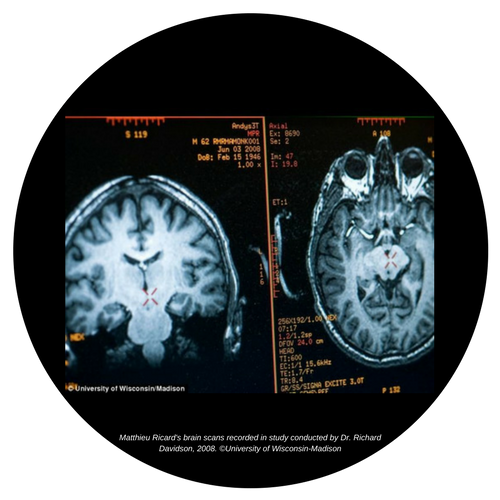

Stressresistenz beginnt im Gehirn

Mittels Magnetresonanztomographie konnte bei Teilnehmern von Meditationskursen gezeigt werden, dass sich die Dichte der sogenannten grauen Gehirn-Substanz erhöht hatte. Die Bilder zeigen, dass bereits eine kurze Übungsphase von etwa 25 Stunden zu nachweisbaren Veränderungen in den Gehirnarealen führt. Betroffen sind Bereiche, die für Angststeuerung, Lernprozesse, Selbstwahrnehmung und Stressempfinden zuständig sind.